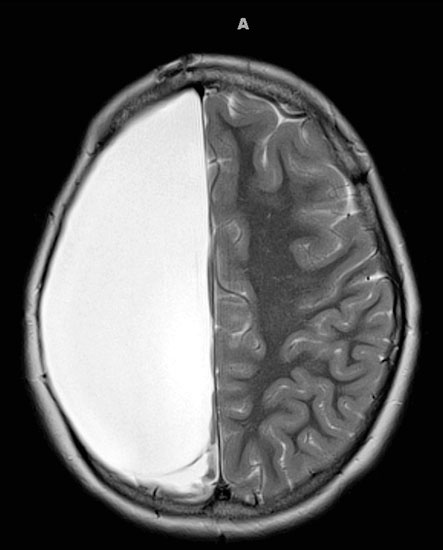

Рассмотрим случай маленькой девочки по имени Кэмерон Мотт. В четырехлетнем возрасте у нее начались сильные судороги. Припадки были агрессивными: Кэмерон внезапно бросалась на пол, требуя, чтобы на нее надели шлем. У нее довольно быстро диагностировали редкое истощающее заболевание, которое называется энцефалитом Расмуссена. Врачи знали, что эта разновидность эпилепсии приводит к параличу и в конечном итоге к смерти, и поэтому предложили рискованное хирургическое вмешательство. В 2007 г. в результате операции, длившейся двенадцать часов, хирурги удалили почти половину мозга девочки.

Каковы же долговременные последствия удаления половины мозга? Они оказались на удивление незначительны. У Кэмерон одна половина тела слабее другой, но в остальном девочка практически не отличается от одноклассников. У нее нет проблем с пониманием речи, музыки, математики и литературы. Она хорошо успевает в школе и занимается спортом.

Иллюстрация к книге — Мозг. Ваша личная история [i_084.jpg]

На изображении мозга Кэмерон белое пространство – отсутствующая половина мозга.

Неужели это возможно? Получается, что половина мозга Кэмерон оказалась просто лишней; вторая половина оперативно перестроилась и взяла на себя утраченные функции, так что вся деятельность сосредоточилась в половине мозга. Выздоровление Кэмерон подчеркивает эту удивительную способность мозга: он перестраивает себя, приспосабливаясь к вводу информации и требуемым действиям, к задачам, которые решаются в настоящий момент.